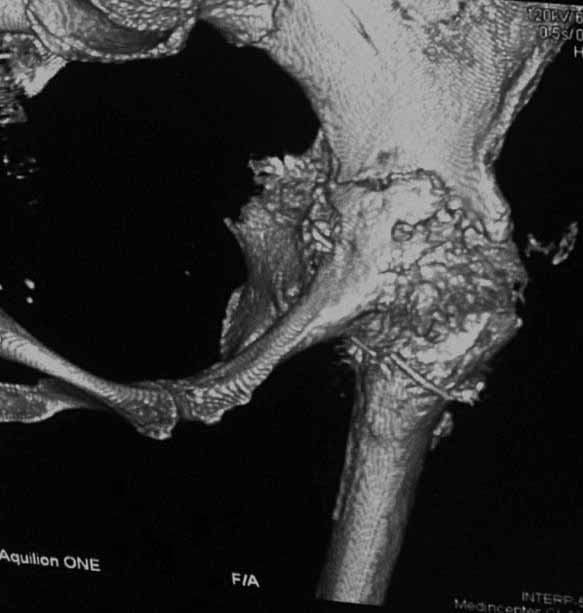

Уважаемые коллеги. Хотелось бы услышать мнения и советы по представляемому случаю. Пациентка 45 лет. Бесцементное эндопротезирование левого тазобедренного сустава 6 лет назад (впадина RM, Mathys, металл-металл, ножка Зульцеровская). За 10 лет до протезирования – коррегирующая остеотомия бедренной кости, которая не срослась в течение года до удаления пластины, а затем срослась в течение 3 месяцев иммобилизации в кокситной повязке. После протезирования получилось наблюдать пациентку почти постоянно, поскольку через 2 года синтезировал ей лодыжки на оперированной стороне, затем, через несколько месяцев удалил фиксаторы, а в 2009г. резецировал мениск на противоположной стороне. Боли все эти годы не беспокоили. Пациентка чуть выше среднего роста, вес тела нормальный. Физические нагрузки переносила хорошо. Работает на 7 этаже без лифта. Год назад экстирпация матки по поводу лейомиомы больших размеров. Несколько месяцев назад появились боли в области левого тазобедренного сустава. При рентгеновском и КТ исследованиях (июль с.г.) – нестабильность тазового компонента. От предложенной замены протеза пациентка на тот момент, слава богу, отказалась. Через какое то время боли в области левого тазобедренного сустава практически полностью прошли, а около 2 месяцев назад появилось ощущение патологической подвижности таза и боли в паху справа, которые через некоторое время уменьшились, а потом снова усилились после значительных физических нагрузок (много ходила по песку на пляже, носила тяжести). Ежедневно принимала диклофенак. На рентгенограммах – переломы правой лонной кости. Сейчас госпитализирована из-за болей в паху справа. Боли слева не беспокоят. На фоне снижения нагрузок в стационаре боли значимо уменьшились. Способна ходить без средств дополнительной опоры.В анализах крови чуть повышены трансаминазы и гамма-ГТ, моча без особенностей.

Вопросы: -правильно ли я расцениваю переломы как стрессовые на фоне неполноценного таза (pelvic insufficiency stress fractures)? -Можно ли так же расценить ситуацию на стороне протеза и, соответственно, не торопиться с ревизией, рассчитывая на вторичную стабилизацию? Уж больно не хочется менять ножку. -Если думать о ревизии, то когда? На представленных снимках тазобедренный сустав до и сразу после операции, затем 2 снимка 2009г., когда ничего не беспокоило, затем КТ 2-х месячной давности и вчерашние рентгенограммы обоих тазобедренных суставов.

Сергей, очень возможно, что перелом и стрессовый, но мне видится, что его причина в нестабильности чашки. Дело в том, что в отличии от ножек, чашка при своей дестабилизации болит гораздо меньше и больные терпят до последнего.

При сравнении рентгенограмм можно увидеть насколько чашка переместилась от места своего первичного расположения. От опрокидывания ее удерживают конструкционные элементы "рожки". Без них ситуация, возможно, уже была бы катастрофической (чашка в тазу). Думаю надежды на вторичную интеграцию, могут быть обмануты и ревизии не избежать.

Если говорить о ревизии, то просто не будет и вероятность установки реконструктивного кольца достаточно высока, однако можно попробовать установить бесцементную высокопористую (для вторичной стабилизации врастанием) чашку с винтами , а по ходу операции решить вопрос о необходимости стабилизации таза пластиной.